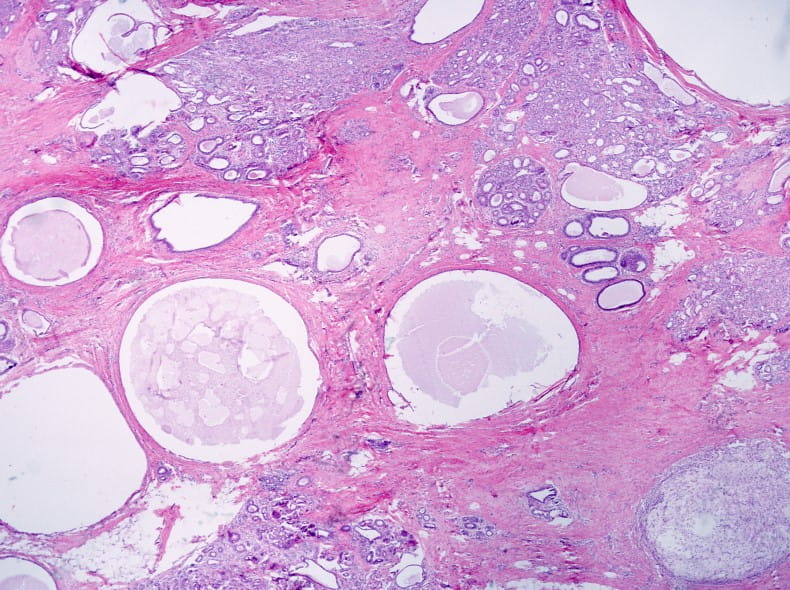

- Fibrocystic disease